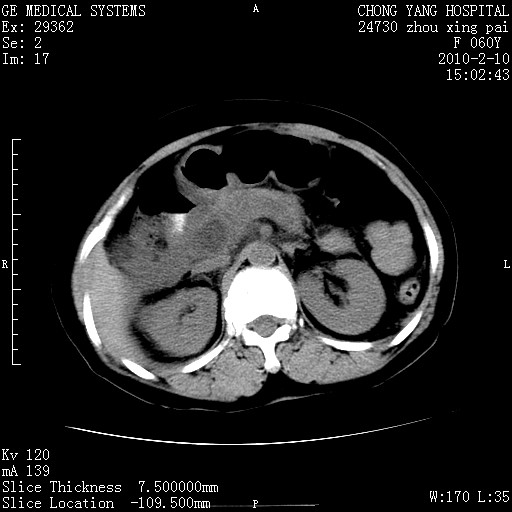

标题: CT24682:F60Y 腹痛 其它不详 [打印本页]

标题: CT24682:F60Y 腹痛 其它不详

1)胆总管末端梗阻,不排除结石所致可能。2)胰腺炎。3)慢性胆囊炎可能。4)左侧输尿管上段扩张。5)少量腹水。6)双侧少量胸腔积液,伴两下肺部分肺萎陷。

1)胆囊炎。2)胆源性胰腺炎。3)右肾周筋膜增厚,肾旁前间隙积液。4)左侧输尿管上段扩张。5)少量腹水。6)双侧少量胸腔积液,伴两下肺部分肺膨胀不全。

1)胆总管末端梗阻。2)胰腺炎。3)慢性胆囊炎可能。4)左侧输尿管上段扩张。5)少量腹水。6)双侧少量胸腔积液,伴两下肺部分肺萎陷。